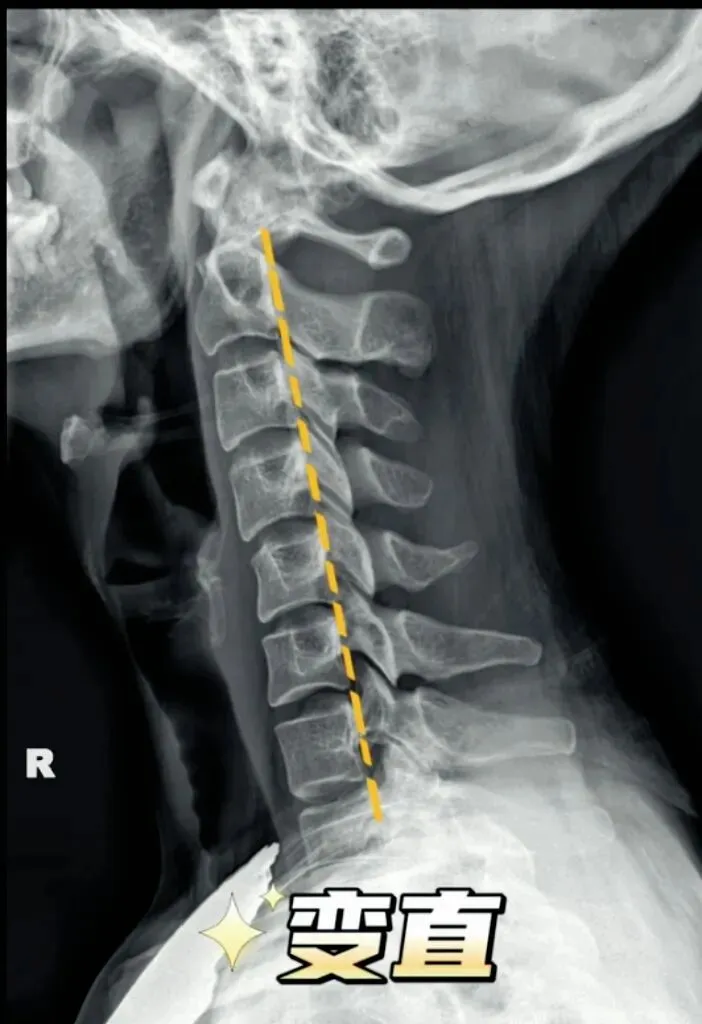

二弓指的是颈椎生理曲度,在颈椎侧位X线片中,正常生理状态下呈现向前凸出的弧形曲线,呈半C型前凸类似弓形,是人体脊柱生理曲度的重要组成部分。颈椎曲度变化能够反映颈椎整体功能的变化。

常见的颈椎曲度改变有曲度变直和曲度反曲。

颈椎生理曲度测量的方法多种多样,其中应用最广泛的测量方法是Borden法。从齿状突后上缘开始向下将每个椎体后缘相连成为一条弧线,然后从齿状突后上缘至C7椎体后下缘作一直线测量,两条线间最宽处的垂直横交线的距离即为颈椎生理曲度深度。

正常时,最宽处在C4椎体水平正常为12毫米,正负5毫米,小于7毫米为生理曲度变直,大于17毫米为生理曲度过度前屈,小于零时为生理曲度反曲。